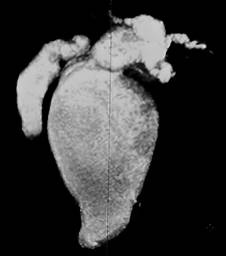

Figura 4: Colangiografía por resonancia magnética. Reconstrucción 3D de colangioresonancia magnética: ensanchamiento de colédoco de hasta 70 mm, dilatación del conducto hepático derecho con 18 mm y 15 mm del conducto hepático izquierdo, 30 mm en la zona de confluencia.

Hallazgos: vesícula biliar atrófica sin presencia de cálculos biliares, quiste de 7.6 mm en el conducto cístico, dilatación sacular de la vía biliar intra y extrahepática con un diámetro de 18 mm en el hepático derecho, 15 mm en el hepático izquierdo y una zona de confluencia de 33 mm (carina). Se observó una máxima dilatación del colédoco de 70 mm, colédoco distal de 23 mm y el conducto de Wirsung con dimensiones normales.